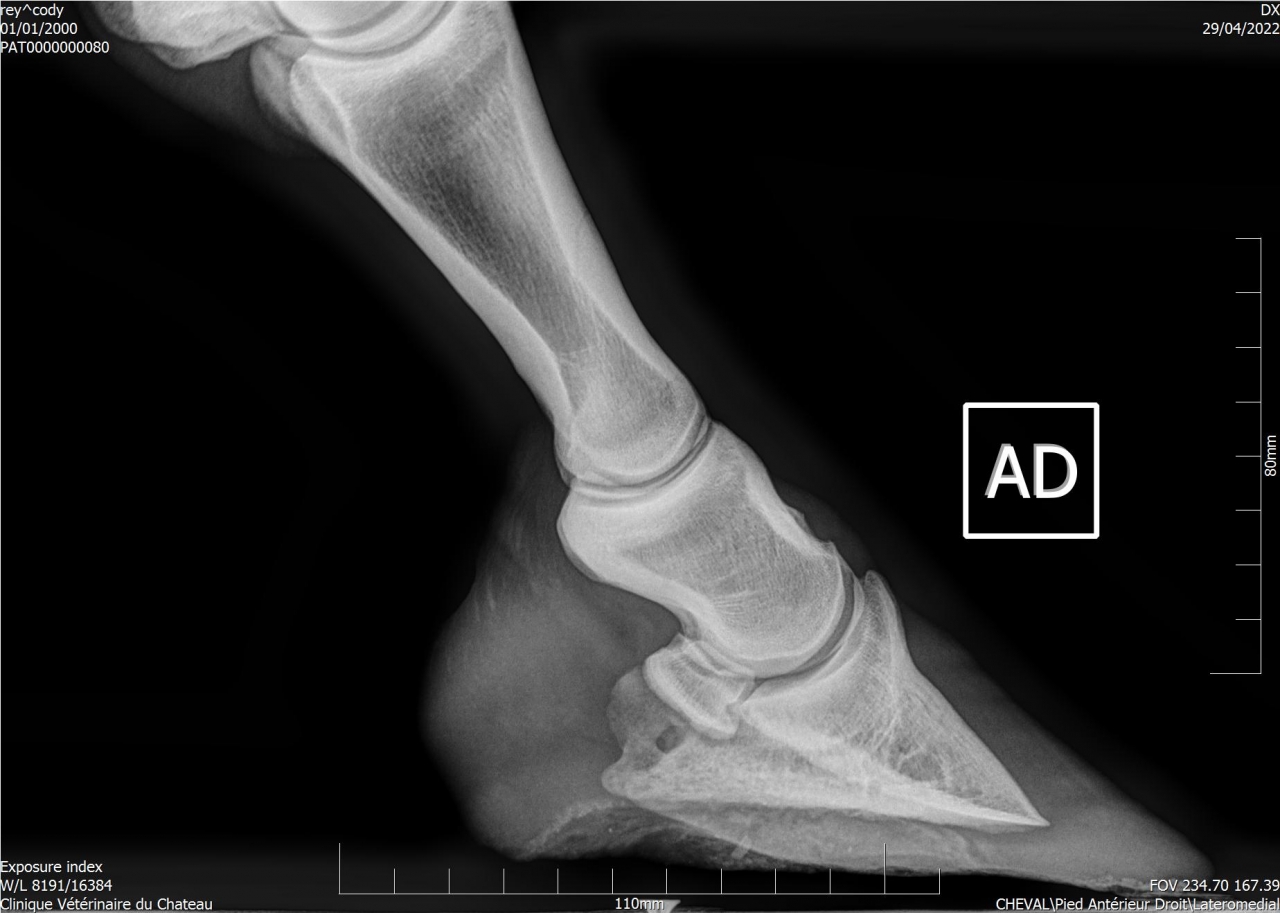

| Dire merci | Suite aux radios faites sur Cody, j'ai fait passer un véto spécialisé en boiteries. Examen : AG paturon légèrement déformé (je n’avais jamais remarqué) Pince + Fers avec oignons et plaques Planche négative (apparemment Cody a bien réagi) Flexions statiques normales Légère irrégularité ADT à main dte (effectivement pas trop mal, ça a été pire) Radiographies fournies : Légère ossification processus palmaires (moi je ne vois rien de particulier sur les radios) Légère arthrose interphalangienne proximale (idem) 1 à 3 fossettes sur chaque naviculaire (apparemment pas catastrophique, le véto m’a montré d’autres radios de chevaux naviculaires pour comparer) Recommandations : Marechalerie : poursuivre à l’identique (Oignons et plaques) Traitement : Dextropine et Navitol Voici les radios : ![]() ![]() ![]() ![]() Si quelqu'un pouvait m’expliquer en termes simples ![]() |

| Dire merci | Je suis pas experte en lecture de radios, loin de là, mais le bord distal du naviculaire semble quand même largement plus vilain que les cartilages palmaires ? Et ça sur les deux pieds.Je serai par contre curieuse de voir des photos du parage vu ce qu’on voit aux radios.. Message édité le 01/07/22 à 22:45 |

| Dire merci | La où il y a les fossettes. En gros la partie en rapport avec le tendon du fléchisseur profond. Mais il a l’air d’être super long au moment des radios? |

| Dire merci | Honnêtement j'ai vu bien pire en ossification des processus palmaires, il faut que je retrouve les radios. Pour le reste je rejoins les autres les pieds sont beaucoup beaucoup trop longs. |

| Dire merci | Je pense qu’un cheval sur deux aura les cartilages plus calcifiés que celui là Peut être même plus… Son plus gros soucis sur les radios c’est quand même l’entretien des pieds. Et c’est le seul facteur sur lequel on peut jouer et qui n’est pas irréversible Faire un parage coûte moins cher que 2 paires de radios |